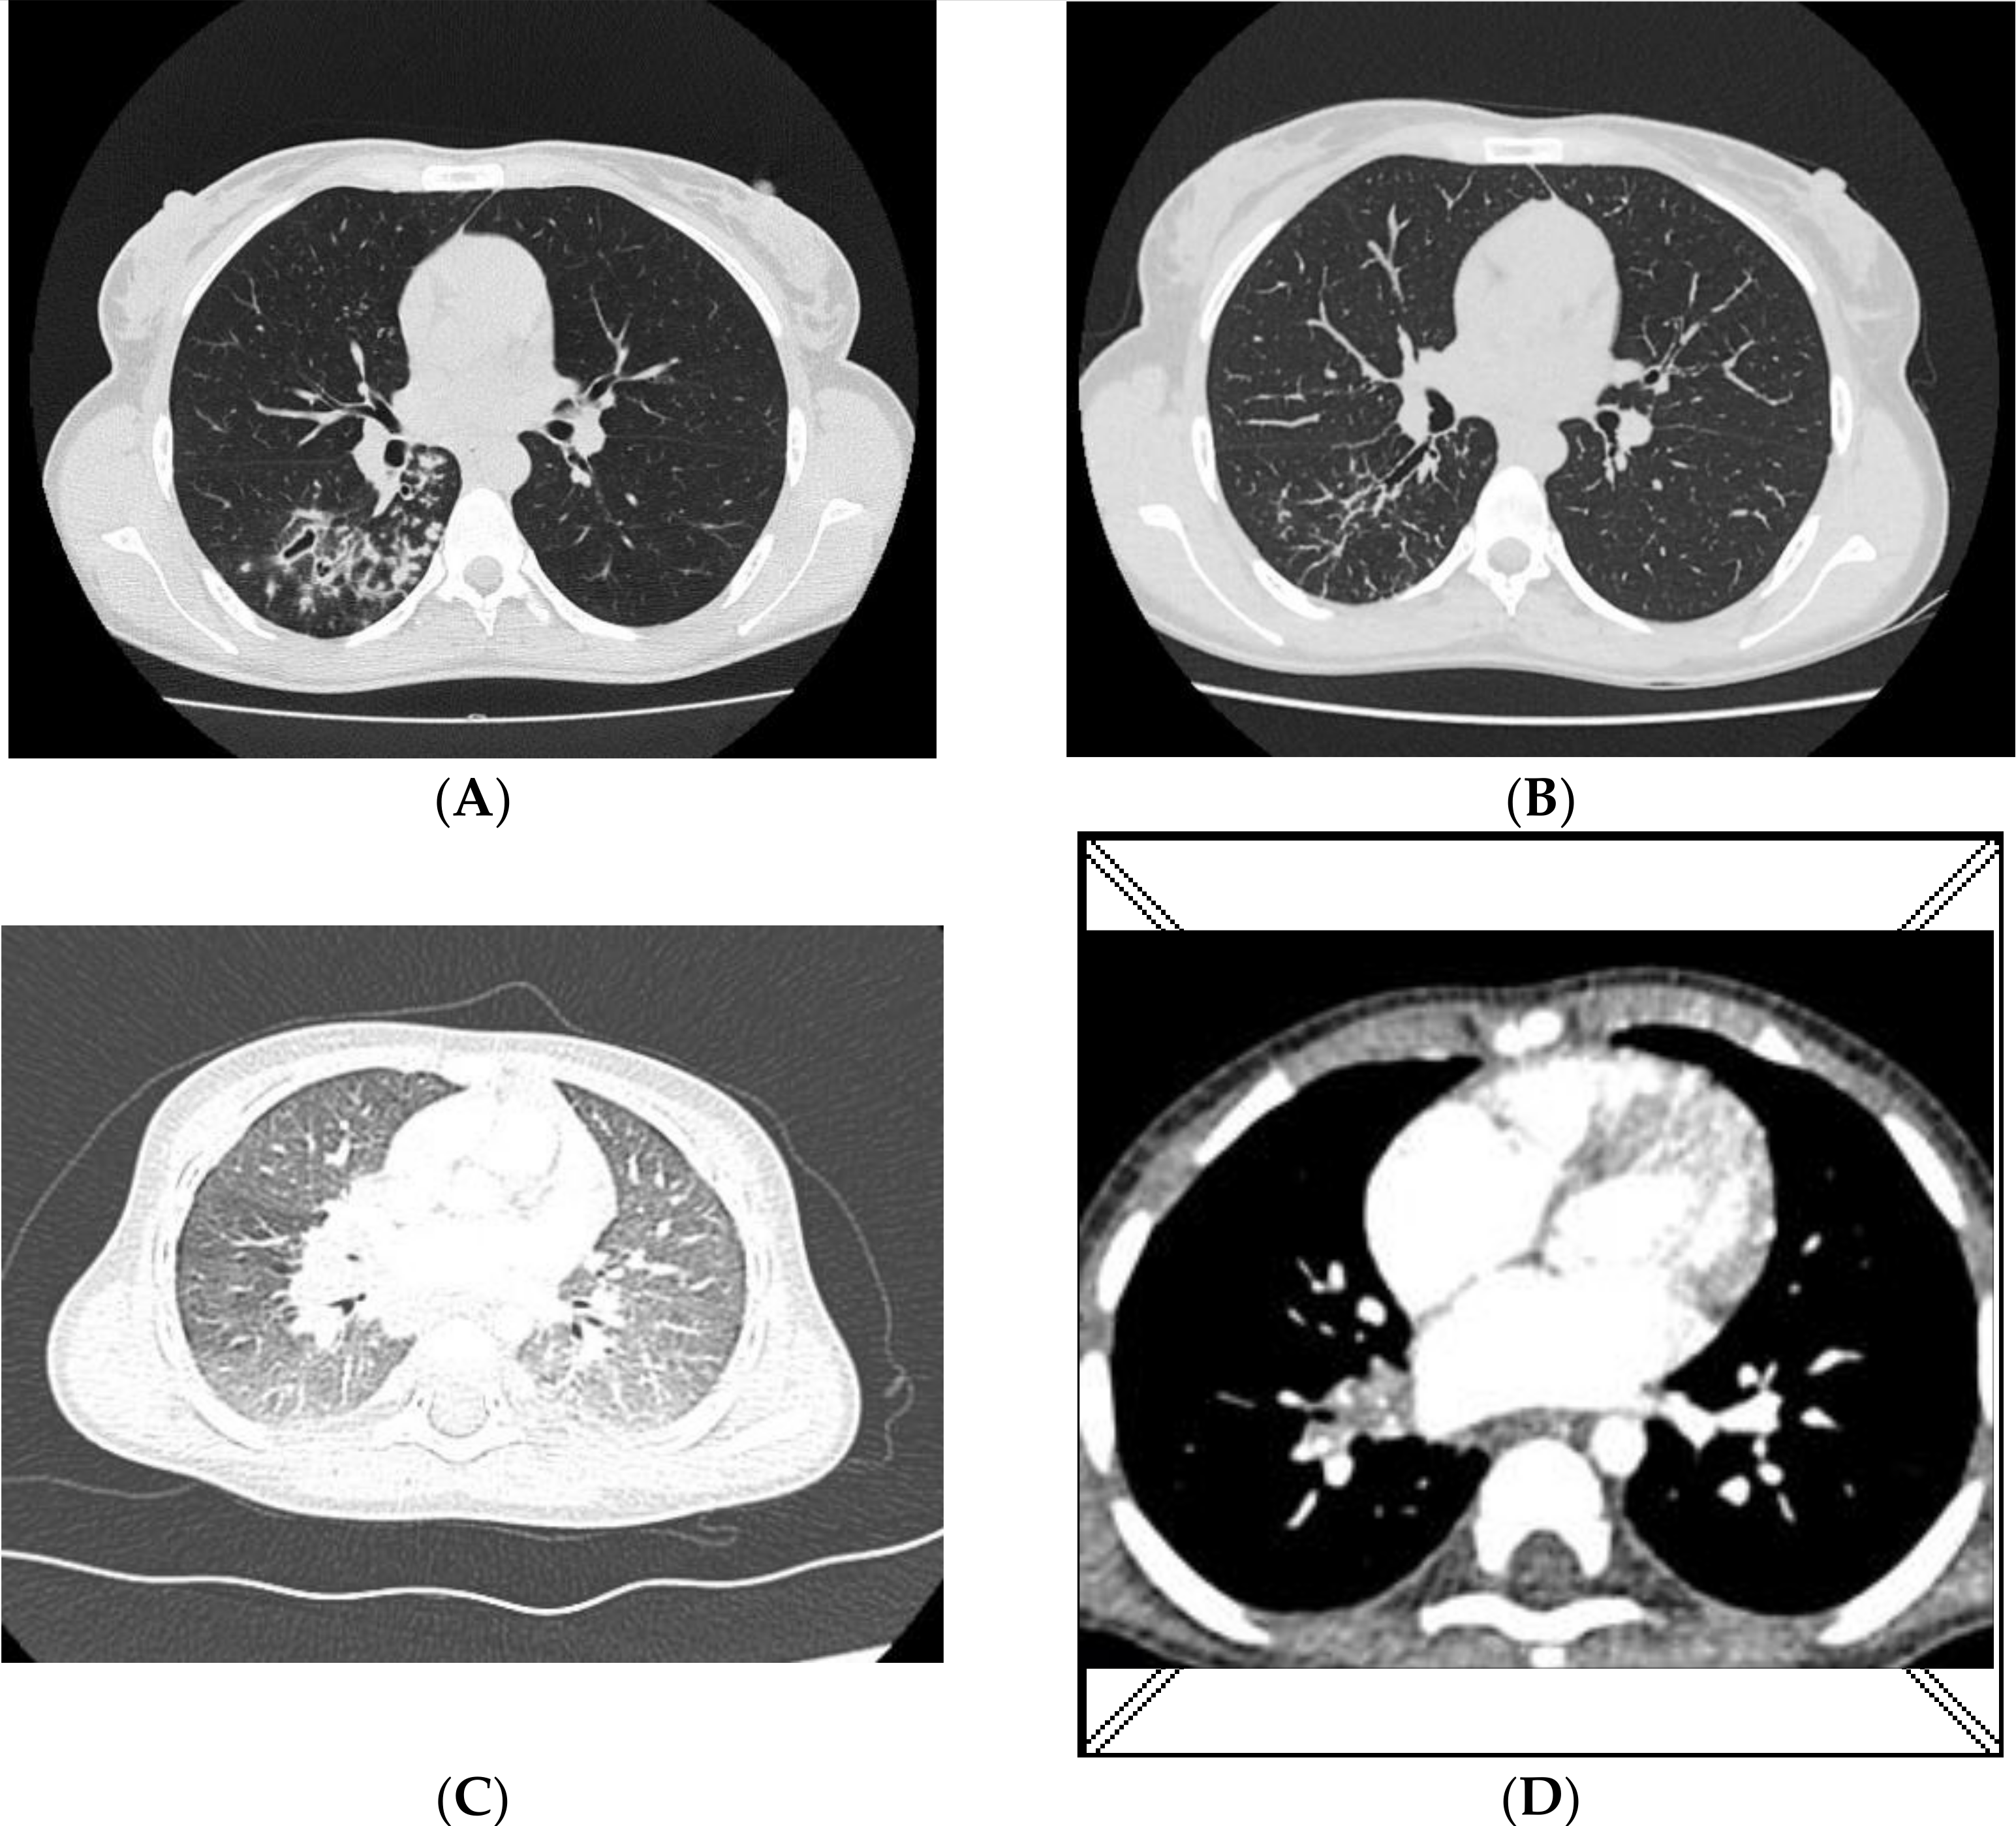

Figure 1.

Chest CT A/B—mother; (A)—nodular lesions in the right lung (3 June 2020); (B)—regression of lesions (5 November 2020); C/D—infant; (C)—ground-glass opacities with some consolidations localized in both lungs (12 June 2020); (D)—regression of lesions, numerous calcifications in the nodes of the right hilum and subcarinal nodes (5 October 2020).

The infant was first examined at the pulmonology outpatient clinic at the beginning of February 2020 when the mother tested positive for mycobacteria in the sputum (AFB+++), and antimycobacterial treatment was initiated, with continued microbiological tests for TB (inoculation on solid and liquid media and an antibiogram). A chest X-ray of the infant did not reveal any lesions in the lungs, and the IGRA (interferon-gamma release assay) was negative. A 3-month prophylactic treatment with isoniazid was initiated. In May 2020, the IGRA was repeated, and the result was positive. The infant was in good health without clinical symptoms. Gastric lavage specimens were sampled three times for microbiological tests. In June 2020, a chest X-ray and CT scan were performed again. Ground-glass opacities were identified in the lungs as well as enlarged lymph nodes in the lung hila and mediastinum (Figure 1C). A bronchoscopy was also performed, and the mucous secretion was aspirated and sent for microbiological tests. Because the infant was in good physical health and had no clinical symptoms, and the fact that the strain isolated from the mother was multi-drug resistant (no guidelines for prophylaxis in children having contact with XDR-TB), treatment was not initiated, and a decision was made to conduct weekly follow-up tests at the pulmonology outpatient clinic.

In July 2020, an MTBC strain was cultured from gastric lavage specimens sampled in May. The cultured strain was identical to the one cultured from the mother: XDR-TB, spoligotype Beijing 265 with MIRU-VNTR code 333654444432658 (Table 1). In October 2020, after a 3-month observation, gastric lavage specimens were collected three times again. Microbiological tests were negative. A CT was also repeated. Compared to the image acquired in June 2020, regression of the lesions was observed (Figure 1D), the lymph nodes decreased in size, and numerous minor calcifications appeared.